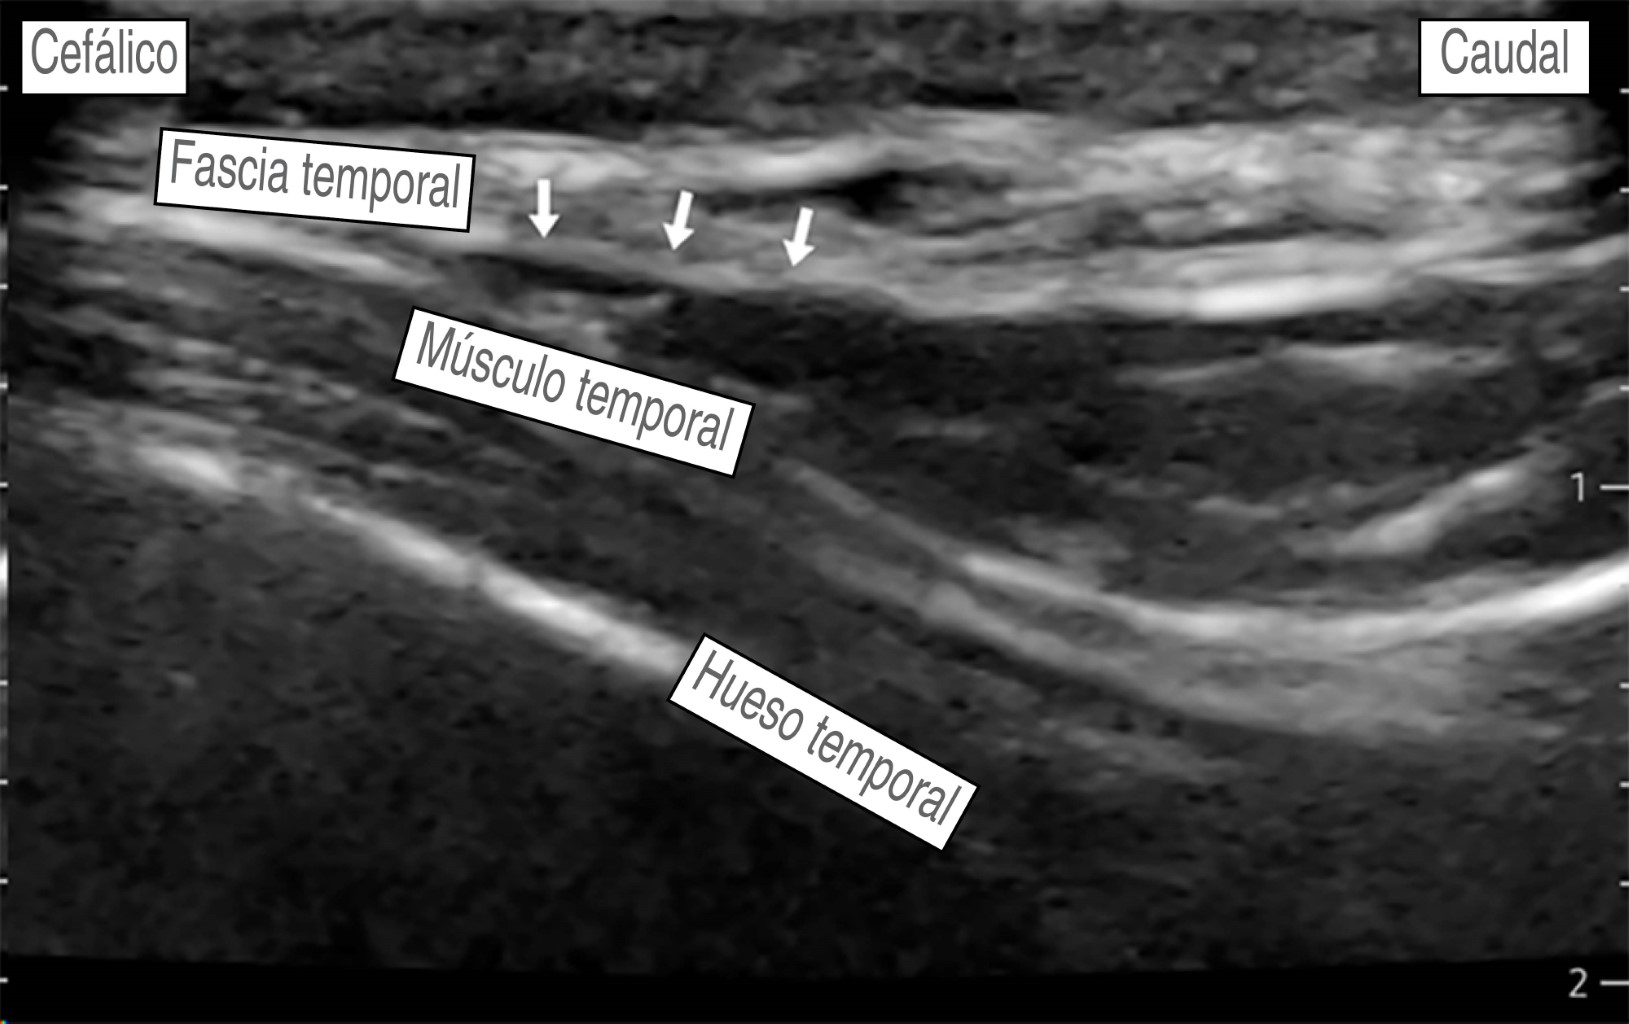

Hombre de 56 años, con diagnóstico de meningioma de la convexidad frontal, con un estado físico de la American Society of Anesthesiologists (ASA) II. Hipertensión arterial esencial en tratamiento regular con losartán 50 mg VO cada 24 horas, sin otros antecedentes. Peso: 87 kg, talla: 1.70 m. Presenta un cuadro clínico de tres meses de evolución caracterizado por cefalea holocraneana, trastornos del comportamiento (apatía, falta de motivación, indiferencia) sin datos de focalización neurológica. La imagen de resonancia magnética muestra una tumoración frontoparietal derecha de 8.2 × 5.1 cm que realza al contraste de forma homogénea, con efecto de masa significativo y desviación de la línea media de 13 mm. Ingresa a sala quirúrgica para craneotomía bifrontal y resección tumoral guiada por neuronavegación. En la sala quirúrgica bajo monitorización invasiva y anestesia total intravenosa con remifentanilo (0.15-0.2 μg/kg/min), propofol (90-120 μg/kg/min), lidocaína (1-2 mg/kg/h) y después de asegurar la vía aérea colocamos un bloqueo de escalpe guiado por USG. Se utilizó una sonda de USG lineal (10 MHz). Nervio supraorbitario y supratroclear: en situación transversal, colocamos la sonda en el hueso frontal sobre el reborde orbitario superior identificando el agujero supraorbitario (muesca). Con técnica en plano, la inyección es superficial al foramen (evitando la administración dentro del foramen), con un volumen de 1.5 mL de anestésico local, para asegurar una cobertura adecuada al nervio supratroclear colocamos otra inyección medial al supraorbitario de 1.5 mL de AL, visualizando su extensión bajo USG. No logramos identificar la arteria supraorbitaria (Figura 2). Nervio cigomático-temporal: colocamos el transductor en un plano coronal, sobre el límite anterior de la fosa temporal, posterior a la apófisis frontal del hueso cigomático, lo que nos deja visualizar tres estructuras: fascia temporal, músculo temporal y hueso temporal, colocamos dos inyecciones de 1.5 mL de AL, en dos puntos de referencia: el hueso temporal (profundo) y la fascia temporal superficial (Figura 3). Nervio auriculotemporal: en el mismo plano facial que el nervio anterior, colocando el transductor en sentido transversal entre el canto lateral del ojo y el trago, identificamos la arteria temporal superficial; el nervio corre en el mismo plano facial que la arteria y lo bloqueamos con 2 mL de AL, evitando la punción vascular (Figura 4). Nervio occipital mayor: colocamos la sonda de USG paralela a una línea que conecta el inión y la mastoides logrando identificar a la arteria occipital junto al nervio. Con inyección en plano utilizamos 2.0 mL de AL (Figura 5). Nervio auricular mayor y occipital menor: bloqueamos ambos nervios a través de un bloqueo de plexo cervical superficial, colocando la sonda transversal sobre la cara lateral del cuello, ubicando el borde posterior del músculo esternocleidomastoideo (ECM) en un punto medio entre la mastoides y la clavícula identificando el plexo como pequeños nódulos hipoecoicos profundos al borde posterior del ECM, el nervio auricular mayor se puede ver comúnmente sobre el músculo ECM. Con técnica en plano la inyección se realizó detrás del ECM, superficial a la fascia prevertebral con un volumen de 5 mL de AL (Figura 6). El bloqueo se realizó de forma bilateral utilizando 28 mL de bupivacaína isobárica a 0.5%, empleando un tiempo de 30 min, se evitó de forma efectiva la respuesta hemodinámica al pinchado, sin necesidad de aumentar la dosis de opioide, o requerir infiltración del área de colocación del pincho, se complementó la analgesia multimodal con paracetamol 1 g IV + ketoprofeno 100 mg IV, no se requirieron rescates de opioide en las 48 horas posteriores y hasta el egreso, se realizó una resección tumoral de 100% sin secuelas neurológicas, no se presentaron complicaciones asociadas al bloqueo de escalpe (punción vascular o déficit nervioso).

Figura 3